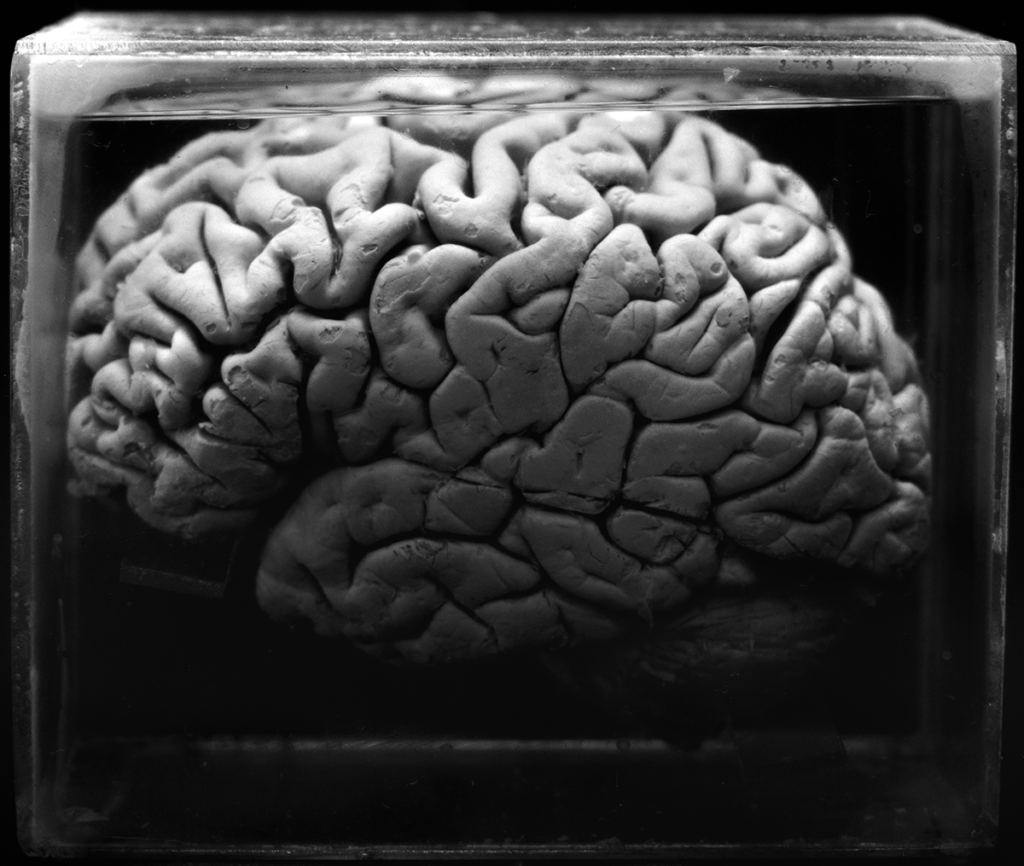

The OJardim series was created using a fictional storyteller that Daniel Malva imagined. The images have names which refer toarche types created by humanity to tell our story. The series has 25 images of human body parts dried or in formaldehyde solution. They were photographed at a collection of anatomy from São Paulo. This work was exhibited in São Paulo in 2015 and the works are in the process of being acquired by the City Museum of São Paulo.

series: OJardim

year: 2014

suport: black and white 5x7” large format film, Giclée on

Hahnemühle Photo Satin 310gsm

edition: 1/6 + 3 Ap

size: 44x52cm

year: 2014

suport: black and white 5x7” large format film, Giclée on

Hahnemühle Photo Satin 310gsm

edition: 1/6 + 3 Ap

size: 44x52cm